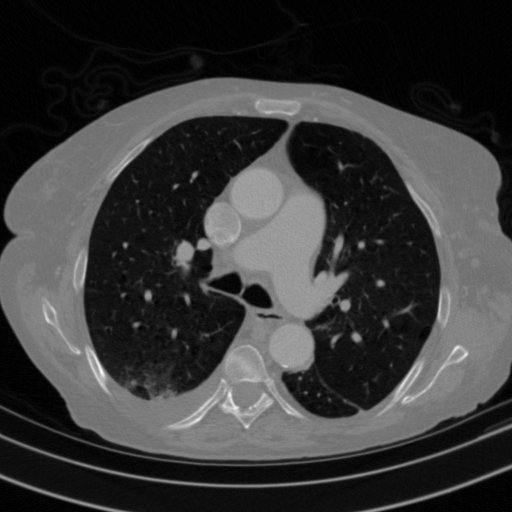

Targeted Slice 70 - HU-Space Analysis (Generated vs Real Venous)

0.762

HU SSIM

169.4

HU RMSE

78.9

HU MAE

Average HU-Space Metrics Across All Slices (153 slices) - Generated vs Real Venous

0.753

HU SSIM (Avg)

155.9

HU RMSE (Avg)

73.8

HU MAE (Avg)

Full window (WL 1023.5, WW 4095 β†’ Low βˆ’1024, High +3071)